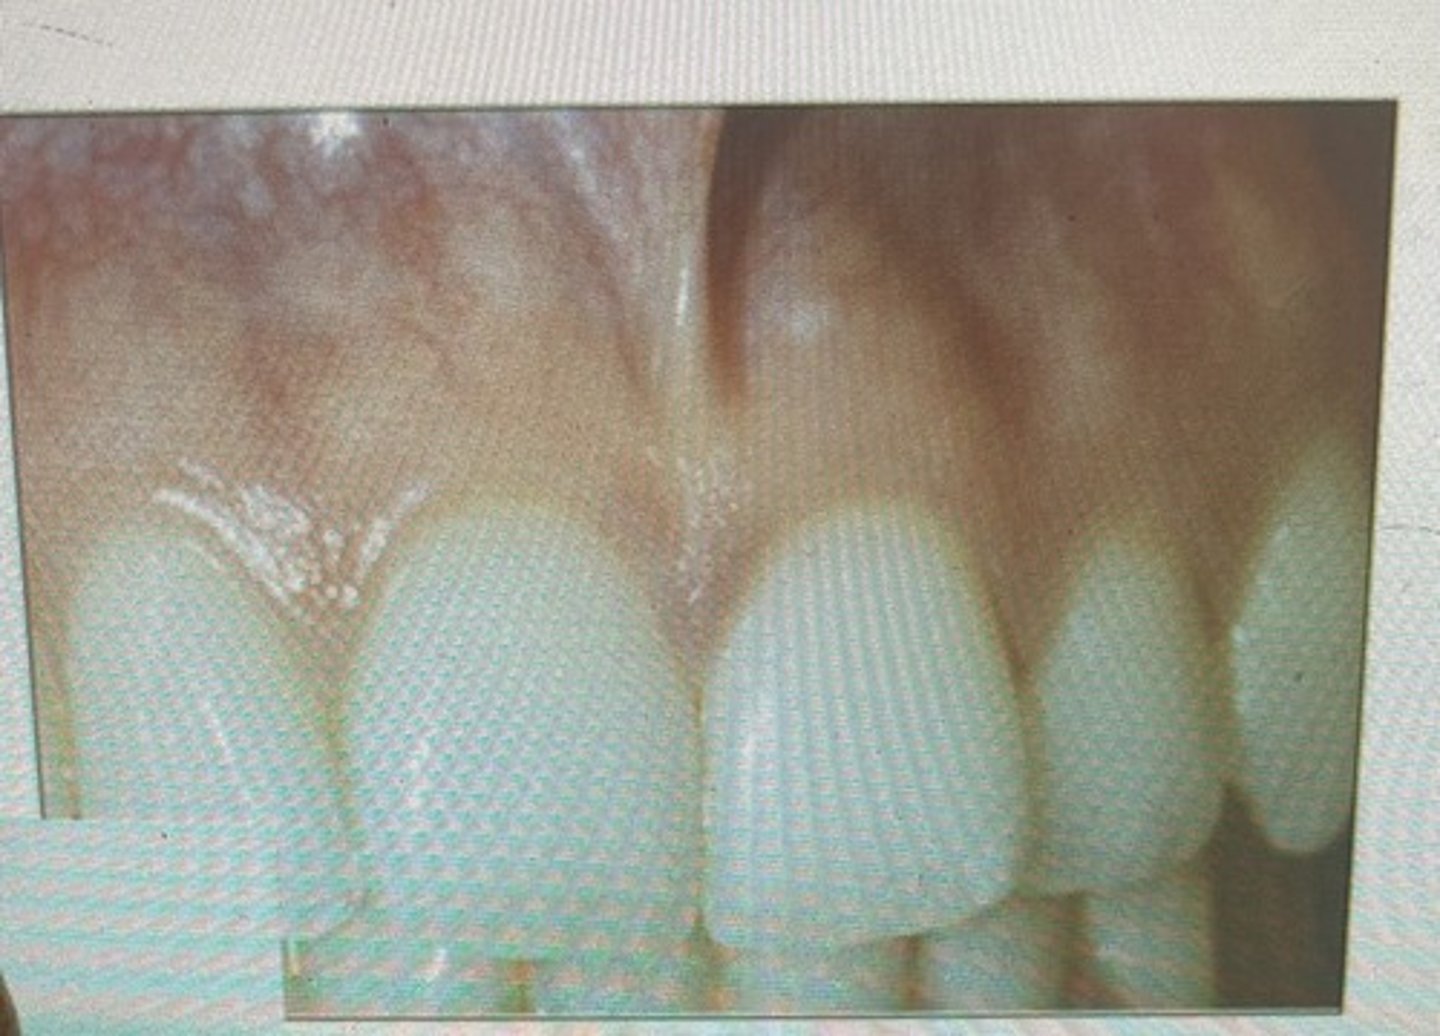

pointed papilla

blunted papilla

bulbous papilla

cratered papilla